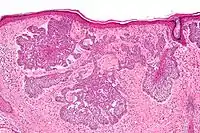

Nodular basal-cell carcinoma

Nodular basal-cell carcinoma (also known as "classic basal-cell carcinoma") accounts for 50% of all BCC.[21] It most commonly occurs on the sun-exposed areas of the head and neck.[22]:748[23]:646 Histopathology shows aggregates of basaloid cells with well-defined borders, showing a peripheral palisading of cells and one or more typical clefts.[21] Such clefts are caused by shrinkage of mucin during tissue fixation and staining.[24] Central necrosis with eosinophilic, granular features may be also present, as well as mucin. The heavy aggregates of mucin determine a cystic structure. Calcification may be also present, especially in long-standing lesions.[21] Mitotic activity is usually not so evident, but a high mitotic rate may be present in more aggressive lesions.[21] Adenoidal BCC can be classified as a variant of NBCC, characterized by basaloid cells with a reticulated configuration extending into the dermis.[21]

Cleft.